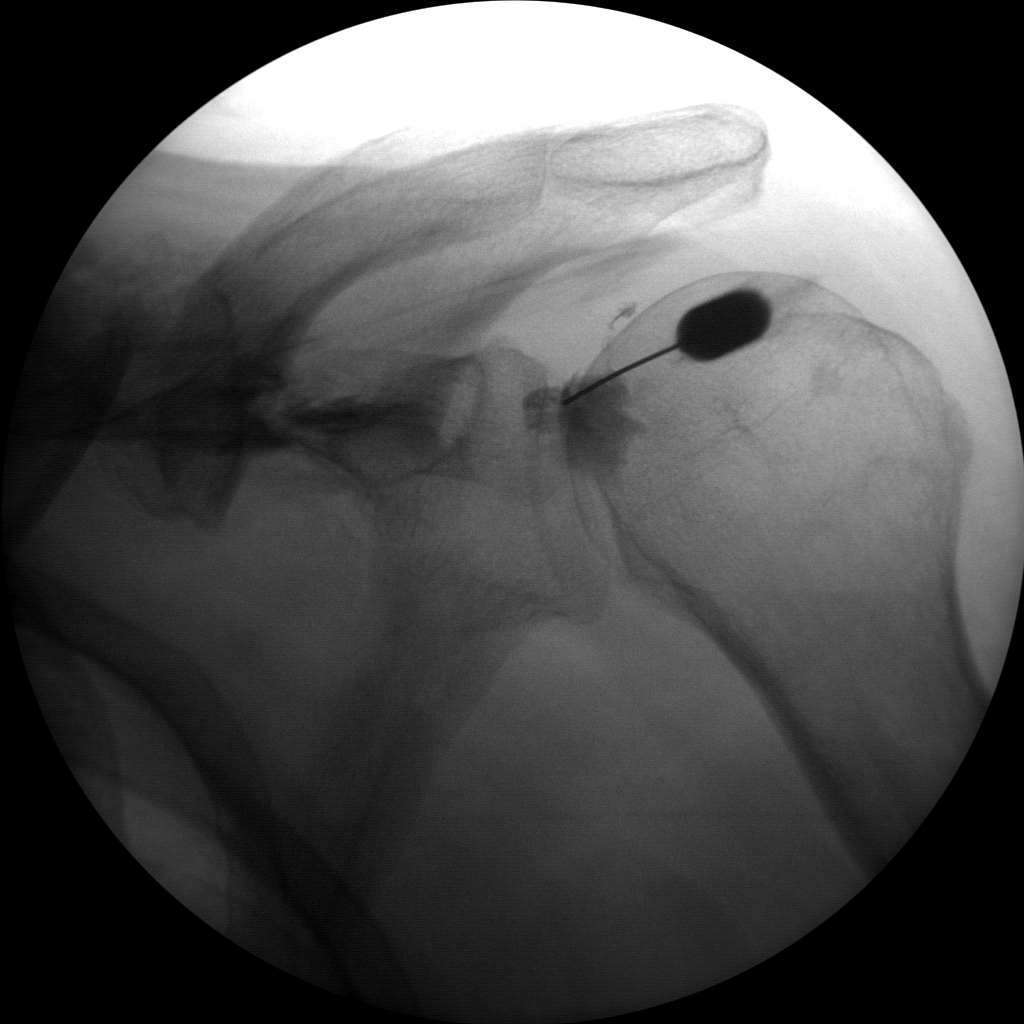

The vascular package comes standard with Skan-C that enables clinics and ambulatory surgery centers to perform a wider range of procedures, including DSA and roadmap. These packages typically include specialized imaging modes, tools, and software upgrades that are specifically designed for vascular interventions.

Some of the DSA procedures in which Skan-C is highly effective are

Cerebral & peripheral angiography

Cerebral & peripheral angioplasty

Stenting

Thrombectomy

Embolization

High-quality imaging

Skan-C uses advanced imaging technology, such as pulsed fluoroscopy and digital subtraction angiography, to provide highly detailed images of the affected area. This allows doctors to perform procedures with increased precision and accuracy, and better patient outcome